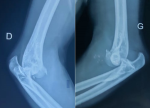

Démarche diagnostique: les radiographies standards ont montré une luxation postéro-externe bilatérale associée aux fractures de la tête radiale et du processus coronoïde (Figure 1). Le patient a été conduit au bloc opératoire en urgence pour une réduction orthopédique sous sédation. Après réduction, des attelles brachio-antébrachio-palmaires bilatérales ont été mises en place en position fonctionnelle, en attendant la prise en charge chirurgicale définitive. Un scanner reconstruction 3D bilatéral des coudes a été réalisé en post-réduction afin de mieux évaluer (Figure 2). La morphologie des fractures de la tête radiale, la taille et la localisation du fragment du processus coronoïde, l'état des surfaces articulaires et des structures associées. Cette imagerie nous a permis de planifier la stratégie chirurgicale adaptée pour chaque coude, notamment en termes de fixation interne et de traitement des fractures de la tête radiale et du processus coronoïde.

Figure 1: radiographie des coudes droit et gauche montrant une luxation postéro-externe bilatérale du coude avec fracture de la tête radiale et du processus coronoïde